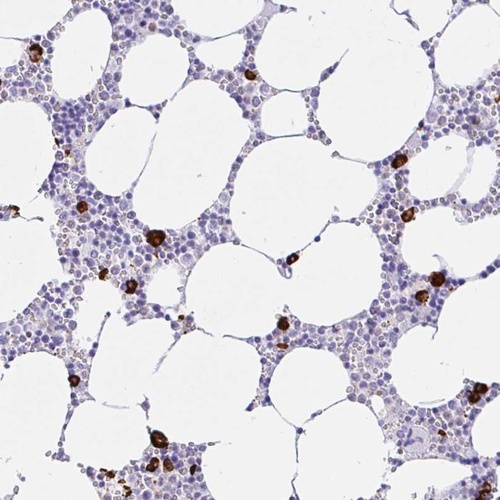

Immunohistochemical staining of human bone marrow shows strong cytoplasmic positivity in hematopoietic cells.